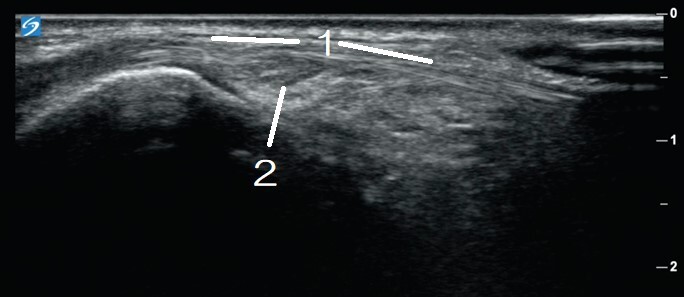

1. Extensor Pollicis Longus (extremely thin tendon)

2. Oblique Cross-section of Compartment 2